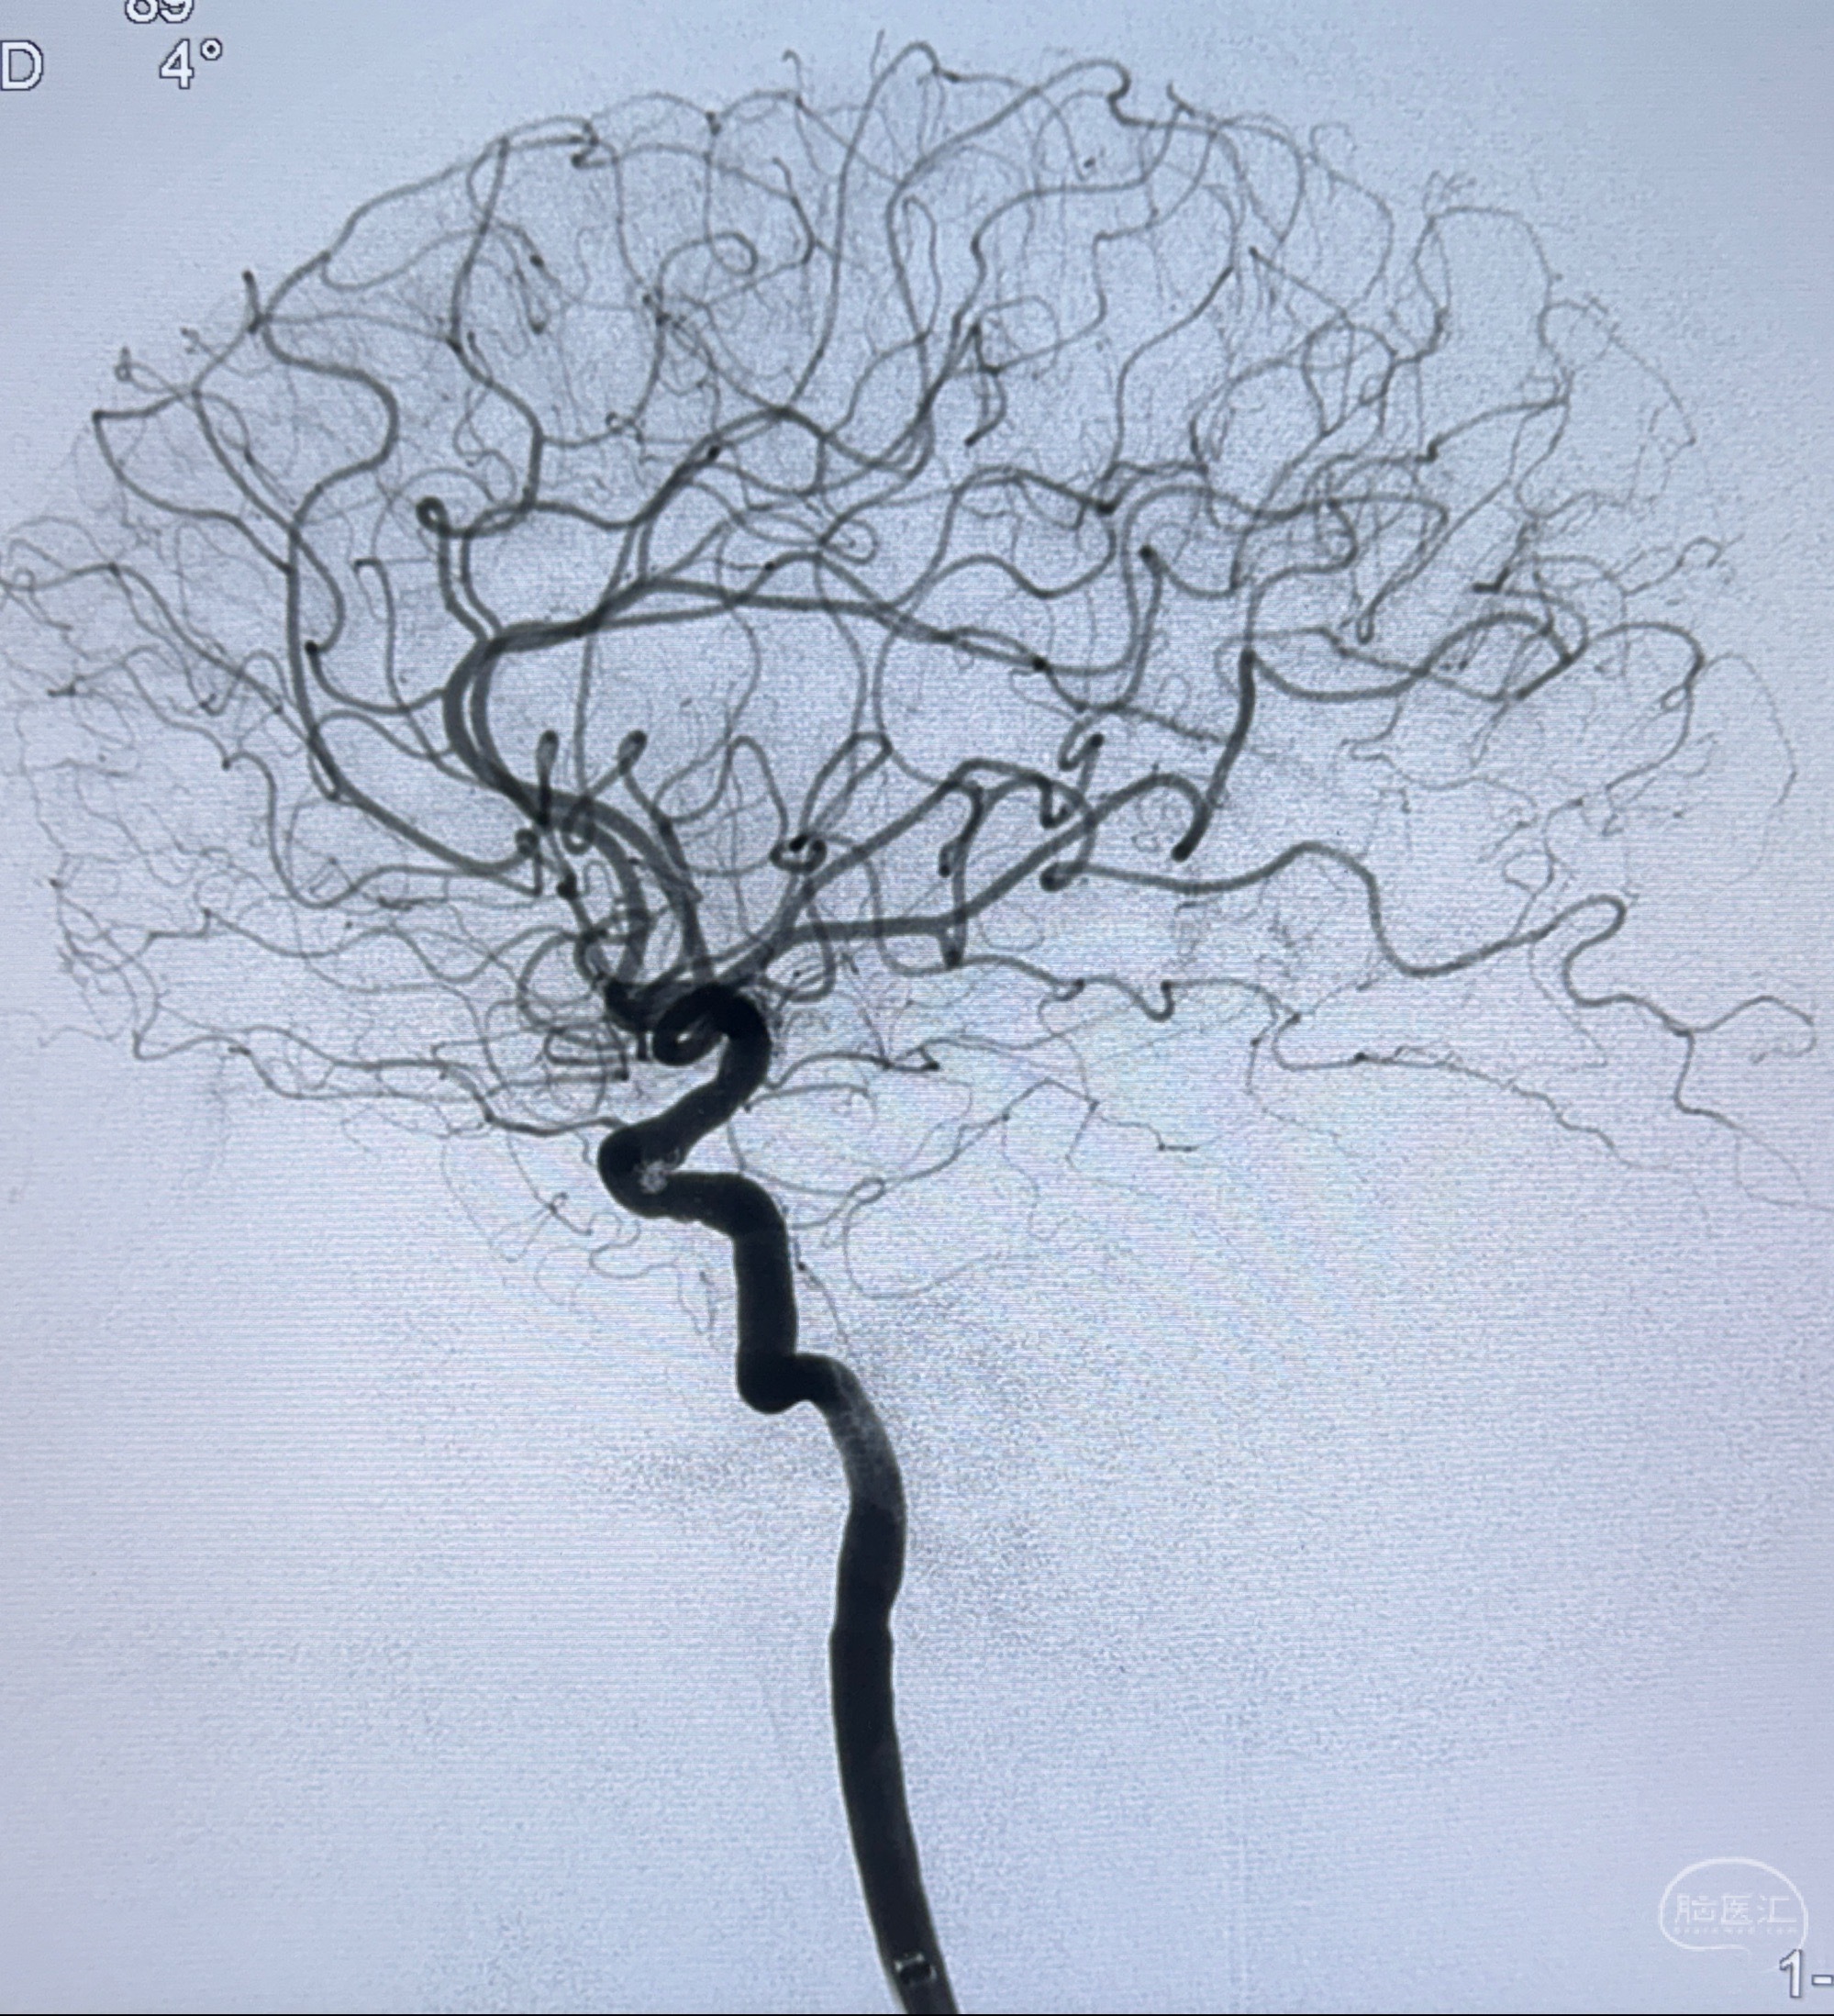

2023-11-13DSA:左侧颈内动脉眼动脉后壁动脉瘤

2023-11-29全麻下行NeuroformEZ4.5-20mm支架辅助栓塞